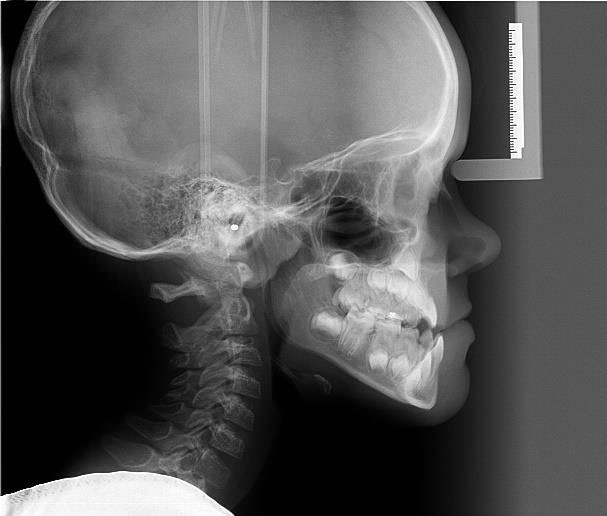

Profesjonalne, bezpieczne badania radiologiczne dla precyzyjnej diagnostyki wad zgryzu oraz stworzenia planu leczenia dopasowanego do potrzeb pacjenta

Ortodoncja posiada własną nowoczesną pracownię rentgenowską, w której bezpiecznie i szybko wykwalifikowany i doświadczony personel wykona wysokiej jakości niezbędne do diagnostyki i planowania badania radiologiczne.

Dobra diagnostyka i diagnoza wykonania na jej podstawie jest warunkiem powstania dobrego planu leczenia.

Aparat ten pozwala na uzyskanie precyzyjnych obrazów 2D dzięki funkcji multilayer i technologii wiązki RTG w kształcie litery V. Badanie może być wykonane w 4 rozdzielczościach obrazu w trybie 3D. Posiada funkcję redukcji artefaktów z metalowych elementów. Ma również 5 wielkości pól obrazowania.